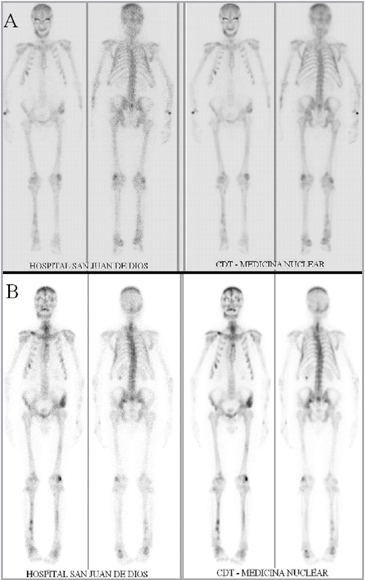

Se complementa estudio con Cintigrama óseo (Figura 3A), que muestra alteraciones cintigráficas difusas y focales del esqueleto, concordantes con enfermedad ósea metabólica y una Ecografía renal que muestra signos de nefropatía médica y litiasis renal bilateral. La evaluación de la densidad ósea mostró a nivel de columna lumbar L2- L4 un Z score de -2,1 y a nivel de cadera izquierda completa un Z score -2,8. (Equipo DEXA Lunar).

Figura 3. A) Cintigrama óseo preoperatorio. B) Cintigrama óseo un año postoperatorio.

Paciente regresa a control un año después de la cirugía, asintomático, sin dolor óseo y deambulando sin dificultad. Sus exámenes de control muestran calcemia 9,7 mg/dl, albúmina 4,0 mg/dl; PTH 20 pg/ml, creatinina 1,7 mg/dl. Además se realiza cintigrama óseo de control (Figura 3B), que muestra alteraciones cintigráficas polifocales de menor intensidad y extensión con respecto al preoperatorio. Al reevaluar la densidad ósea, se evidenció una notable mejoría tanto a nivel de columna lumbar L2- L4 con un Z score de 0,6 como a nivel de cadera izquierda completa con un Z score 0,1. (Equipo DEXA Lunar).